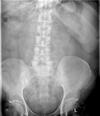

17

AAA